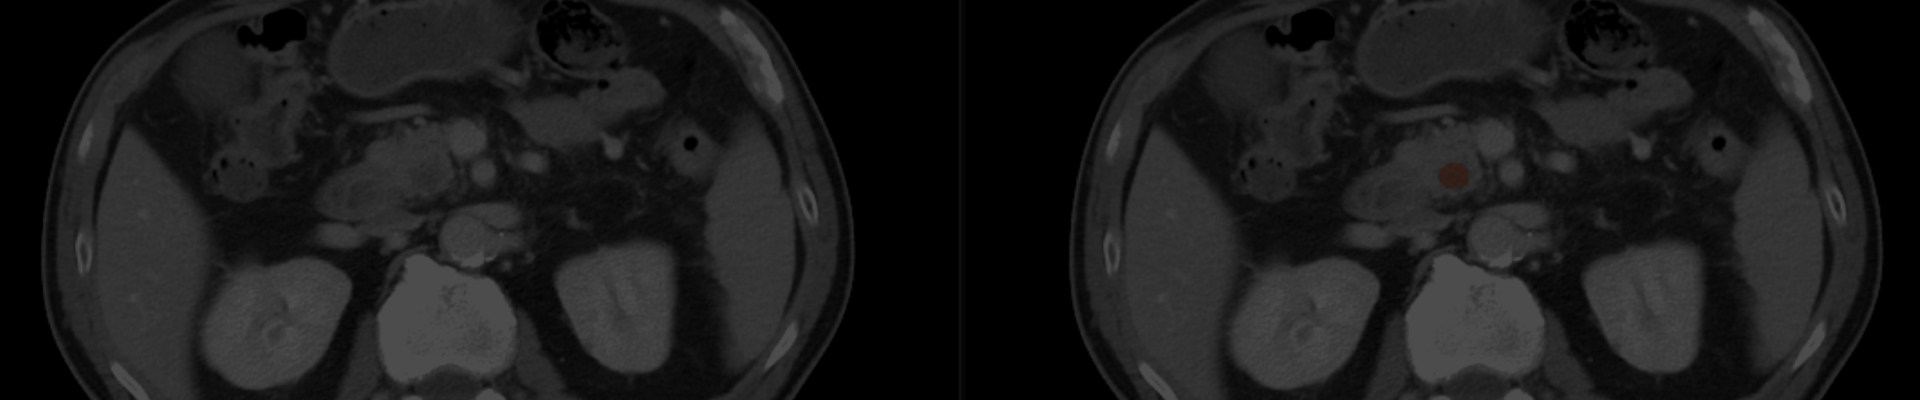

PANCREASaver is an automatic end-to-end tool which determines whether CT images harbor PC.

PANCREASaver identifies missed pancreatic cancer, accurately differentiates subjects with or without pancreatic cancer on CT, and indicates the location of the tumor without requiring manual image labeling or preprocessing.